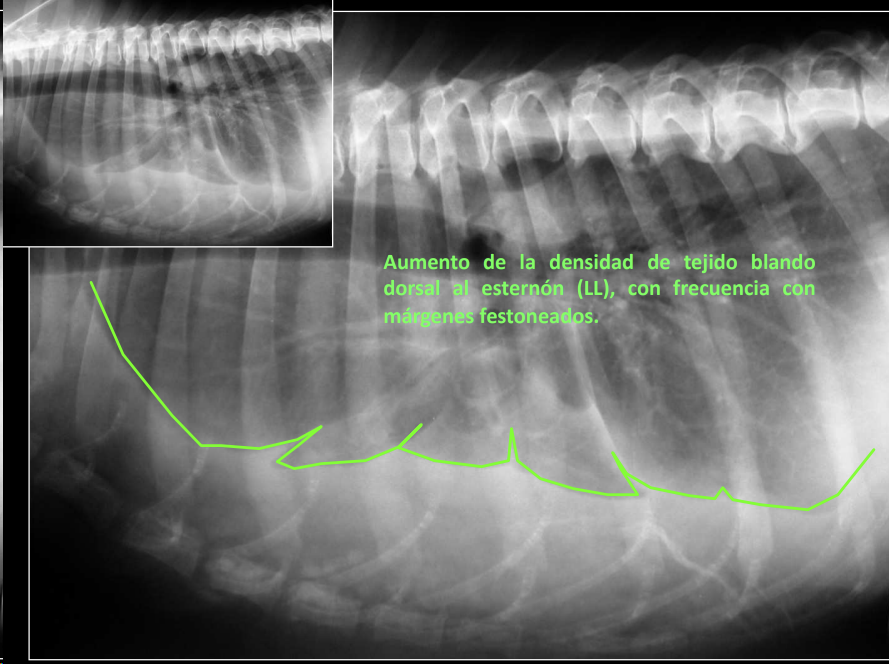

3. Esternón

- Escasas alteraciones significativas.

- Posibles: neoplasias, infección, pectus excavatum (Problemas aspiratorios, puede ser congenita) o pectus perinatum (poco frecuentes, perinatum aun menos)

Cosas que podemos ver:

- Engrosamientos

- Mineralizaciones

- extravasión de aire

- Masas (Dificil de decir si es hematoma, abceso, cuerpo extraño o neoplasia)